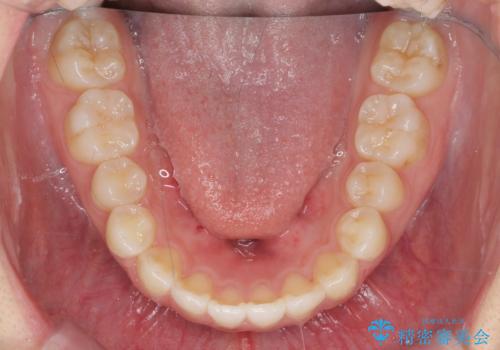

前歯のすれ違い インビザラインで行うマウスピース矯正

- 前歯のガタつき、でこぼこ、前後が逆になっている噛み合わせの改善を求めて来院されました。

治療の装置が目立たず歯ブラシのしやすいマウスピース矯正インビザラインでの治療を計画します。

20時間/日の装用時間をしっかりと守っていただき、きれいな歯並びを手に入れることができました。